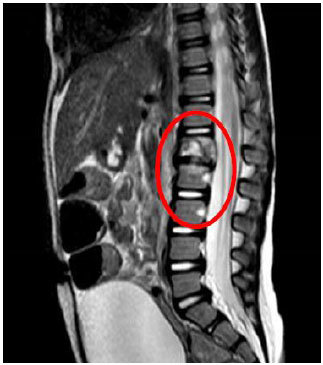

In the case of the missionary with Potts disease (TB abscess on the spine) we needed to get him home from the South African MTC. We were concerned about the layovers on the flights other missionaries would be taking to that country. Quite by accident we discovered there was a direct flight from Johannesburg to his home city (because it is a significant mining city), but we knew he would need help to get home. Because of a wonderful mission president, district president, and especially branch president, we were able to fly the branch president to Johannesburg to accompany the recovering elder back home. To have a branch president with a valid passport was in and of itself a miracle. Needless to say, we definitely see the hand of the Lord in helping these young missionaries be healed from this dreaded disease.